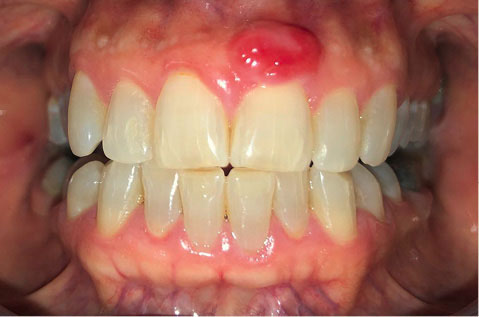

After the graft was separated, it was immediately transferred, the excess clot was removed from the recipient site, and the graft was positioned and firmly adapted with non-absorbable monofilament polypropylene 4-0 sutures (Figure 4).

japid-12-95-g004

Figure 4. Adaptation and suturing of the graft in the recipient zone.